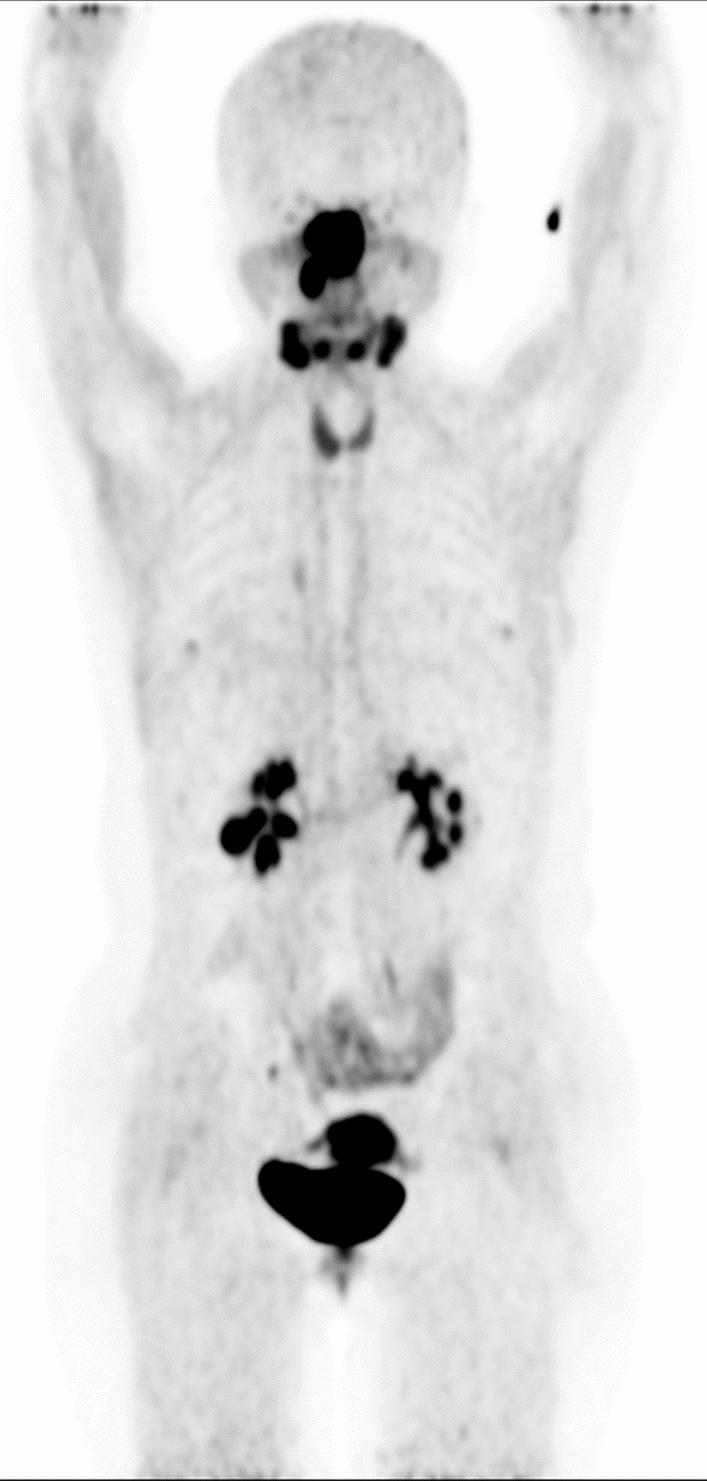

Many patients undergoing [F] AlF-NOTA-FAPI-04 (F-FAPI) PET/CT demonstrated diffuse thyroid uptake. These findings created challenges for accurate interpretation due to the limited understanding of physiological and non-oncologic causes of diffuse F-FAPI uptake in the thyroid. This retrospective study examined patients who underwent F-FAPI PET/CT imaging with diffuse thyroid uptake. It quantitatively assessed normal thyroid uptake, compared F-FAPI uptake between normal and diseased thyroids, and explored potential associations with diffuse thyroid uptake. The study may improve the accuracy of F-FAPI PET/CT interpretation for thyroid and facilitate appropriate management of diffuse thyroid uptake on F-FAPI PET/CT.

A total of 38 patients were included in this study based on the inclusion criteria. The mean SUVmax, SUVmean, and TBR of normal thyroid were 7.09 ± 3.83, 4.24 ± 2.25 and 3.93 ± 1.73, respectively. Quantitative analysis revealed no significant asymmetry in F-FAPI uptake between the right and left thyroid lobes (SUVmax: right 6.69 ± 2.96 vs. left 6.54 ± 3.28, p = 0.84; SUVmean: right 4.19 ± 1.73 vs. left 4.18 ± 1.97, p = 0.98), consistent with the diffuse uptake pattern observed. There was no significant correlation between Hashimoto thyroiditis, serum TSH levels, and the degree of diffuse thyroid uptake (all p > 0.05 for SUVmax, SUVmean, and TBR). Furthermore, no association was observed between sex, age, immunotherapy, and diffuse thyroid uptake (p > 0.05).

CONCLUSIONS

Diffuse uptake of F-FAPI in the thyroid may not significantly relate to Hashimoto thyroiditis or abnormal serum TSH levels. Lesions on F-FAPI PET/CT scans might be hard to detect due to the moderate uptake in normal thyroid tissue.